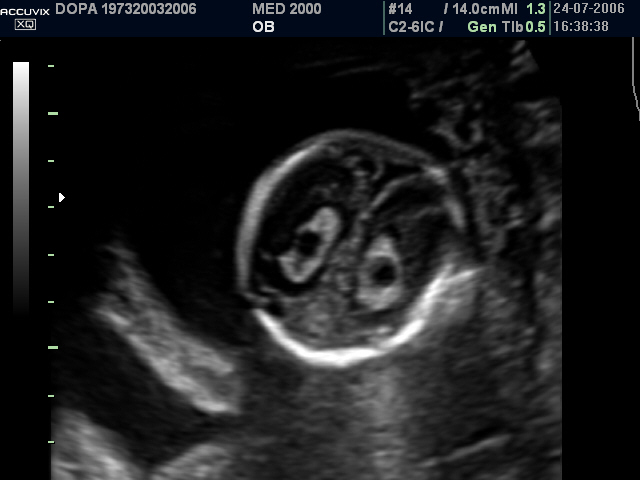

Ecograficamente si presentano come aree cistiche rotondeggianti o ovalari, uniloculari o settate, di diametro variabile da 3 a 9 mm., singole o multiple, monolaterali o bilaterali, localizzate più frequentemente nei plessi corioidei dei ventricoli cerebrali laterali, meno frequentemente nel III e IV ventricolo.